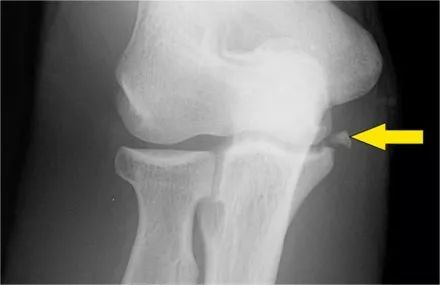

下面的射线照片是一名15岁的棒球运动员,有4年的肘部疼痛史以及最近一次锁定。肱骨小头有一个局部透明度区和一些破碎,这是典型的小头骨软骨病变,

这对于头状骨的是典型的,锁定可能是游离体的结果。